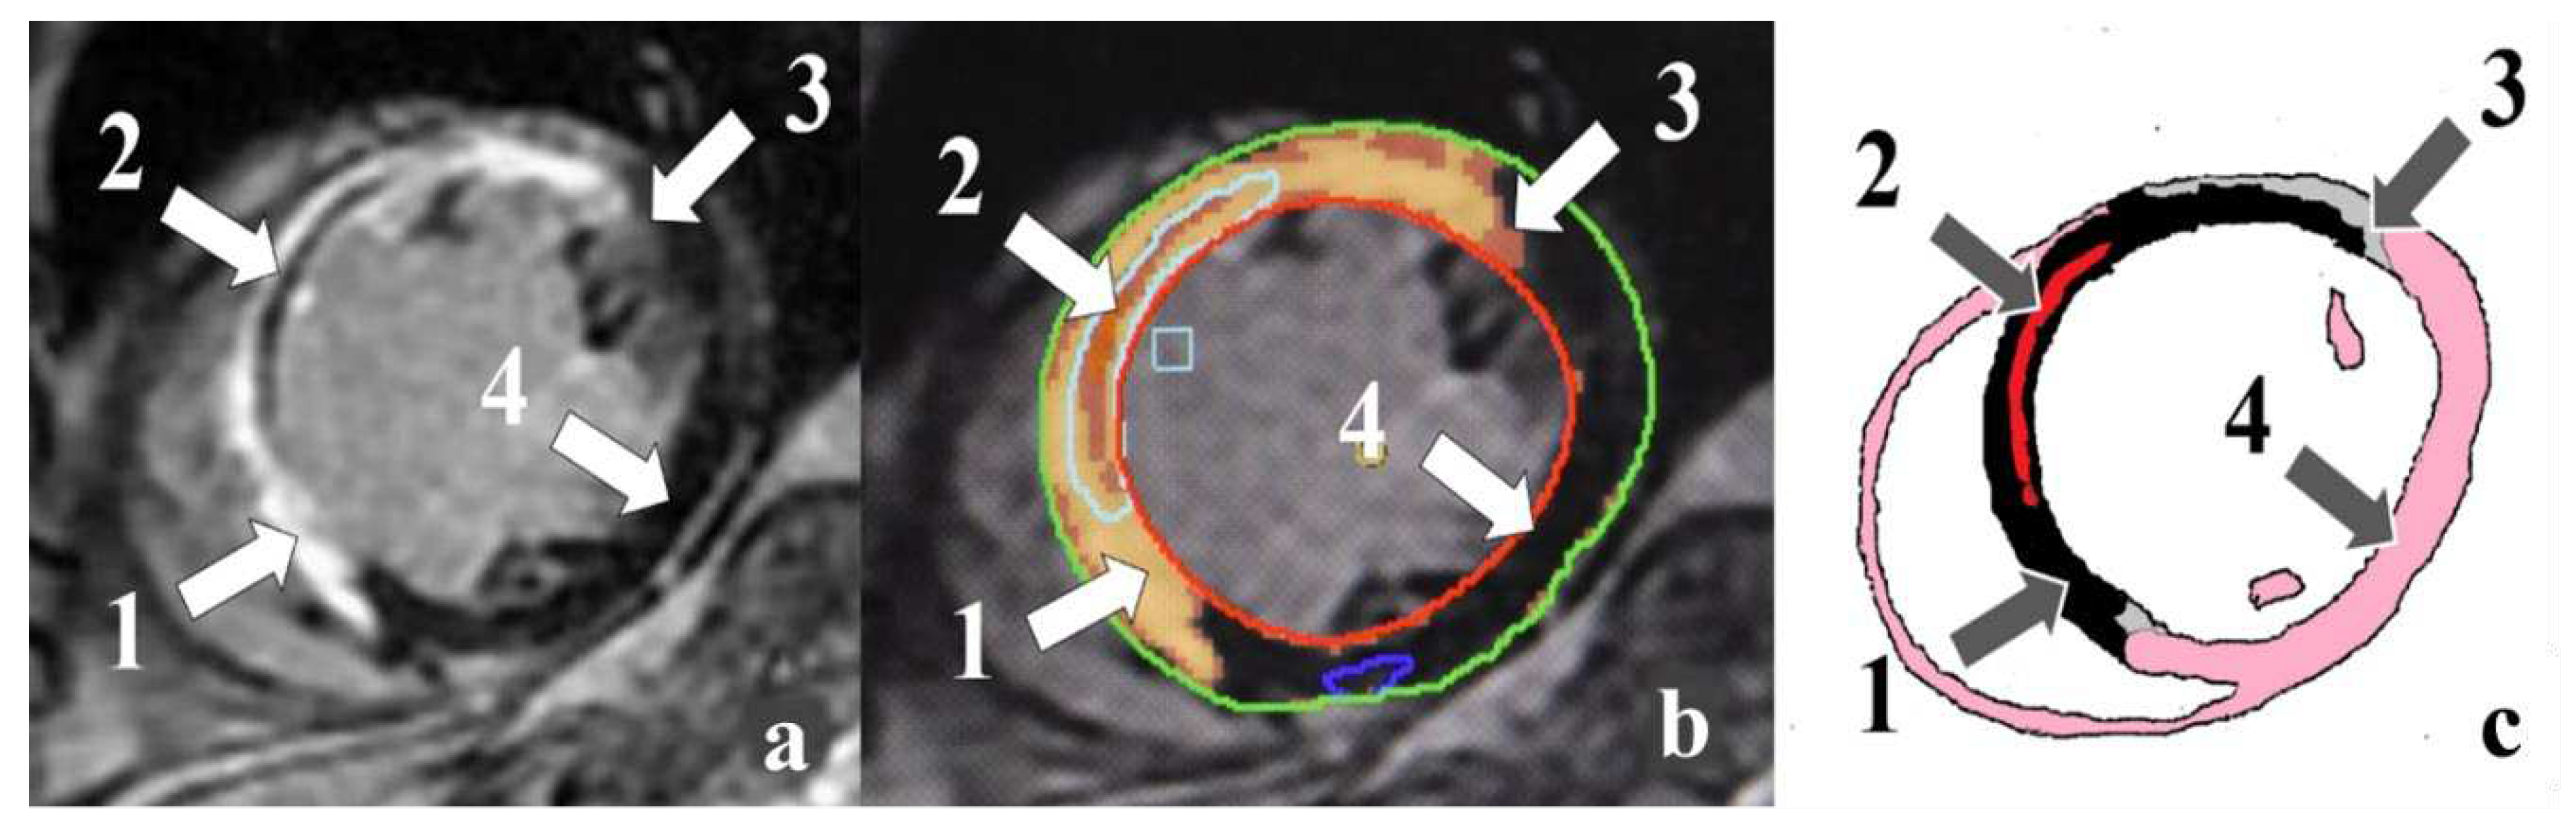

Currently, transthoracic echocardiography is used both for initial assessment of ischemic injury and LV systolic and diastolic dysfunction [7]. An alternative to echocardiography is contrast-enhanced cardiac magnetic resonance imaging (MRI). This method allows estimating LV volumes and functions with high accuracy. Cardiac MRI provides a potential method to characterize scar and peri-infarct zones (PIZ), interstitial edema, microvascular obstruction (MVO), and intramyocardial hemorrhage (IMH) (Figure 1) [8].

Figure 1. Cardiac MRI-based ischemic injury pattern (own observation): a – myocardial delayed enhancement; b – post-processing; c – schematic representation. Infarct zones: 1 – necrosis; 2 –microvascular obstruction; 3 – peri-infarct zone heterogeneity; 4 – intact myocardium.